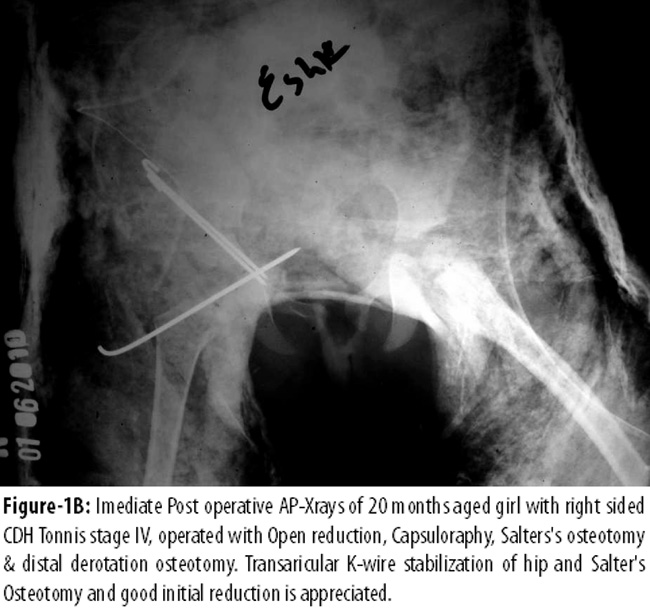

Figure-1B appreciates temporary trans-articular K-wire stabilization of open relocated hip, Salter\'s innominate osteotomy and good initial reduction.